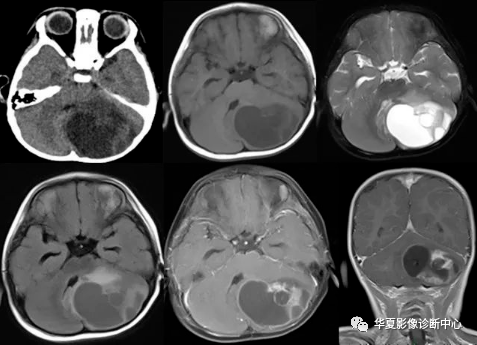

颅内节细胞胶质瘤的mri诊断

图片尺寸720x540